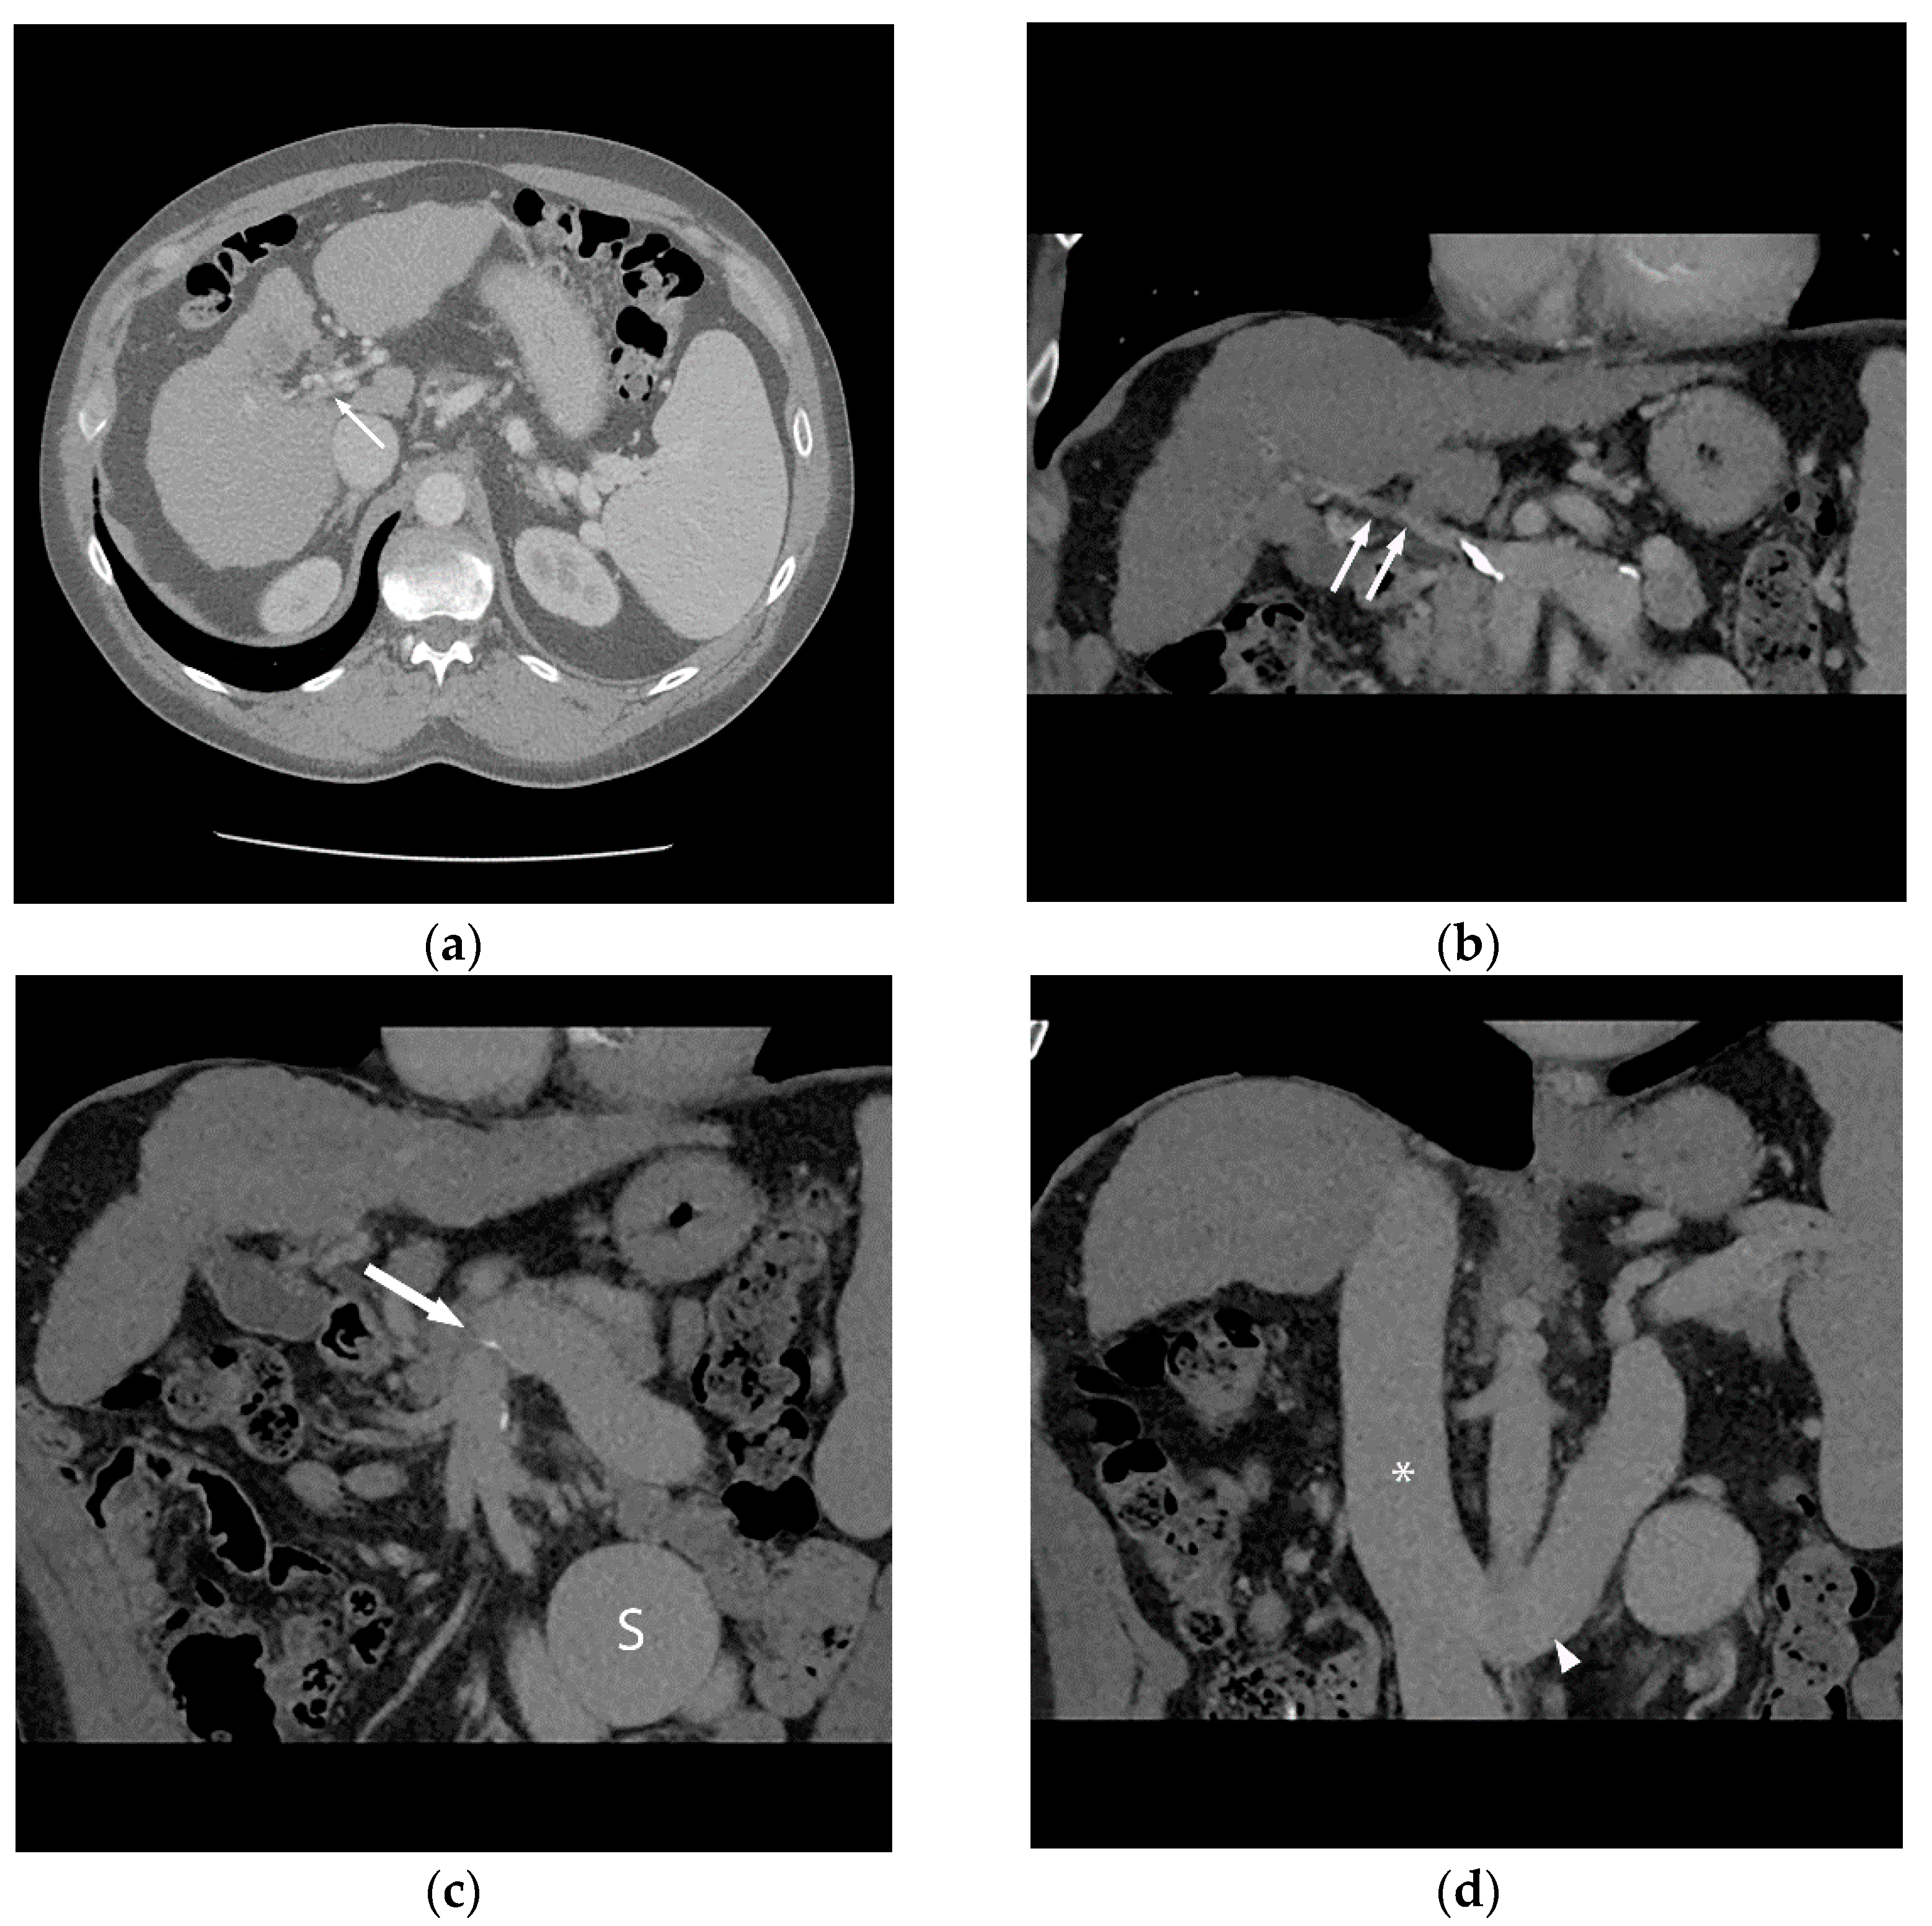

Figure 1.

56-year-old male with history of alcohol-related cirrhosis and portopulmonary syndrome. His baseline values included MELD-Na 19 (Tbili 4.0, INR 2.0, Cr 1.0, Na 137). He had imaging evidence of non-occlusive main portal vein thrombosis. Axial (a) and coronal (b) contrast-enhanced CT shows a diminutive portal vein (arrow). Coronal contrast-enhanced CT (c,d) demonstrates this extended to the portal venous confluence (arrow), with partially visualized component of a large inferior mesenteric vein to gonadal vein portosystemic shunt (S), which drained via the renal vein (arrowhead) to the inferior vena cava (*).